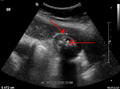

Right upper quadrant abdominal ultrasound is most commonly used to diagnose cholecystitis.[1][22][23] Ultrasound findings suggestive of acute cholecystitis include gallstones, fluid surrounding the gallbladder, gallbladder wall thickening, dilation of the bile duct, and sonographic Murphy's sign.[2] Given its higher sensitivity, hepatic iminodiacetic acid (HIDA) scan can be used if ultrasound is not diagnostic.[2][13] CT scan may also be used if complications such as perforation or gangrene are suspected.[13]

Mild gallbladder wall thickening of 3.5 mm in a person with acute cholecystitis as seen on ultrasound

Acute cholecysitis as seen on ultrasound. Closed arrow points to gall bladder wall thickening. Open arrow points to stones in the GB